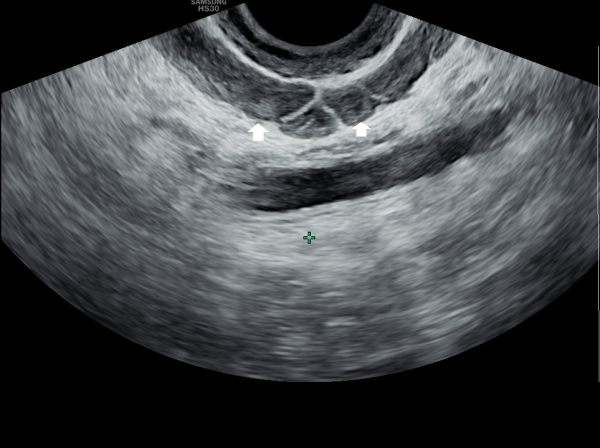

서울가정의학과의원에 첫 내원 당일 지난 5개월동안 회음부 통증과 배뇨장애로 타 비뇨기과 여러곳에서 치료를 했으나 증상의 호전이 없다고 내원 당일 검사한 경직장 전립선 초음파 검사상 사정관 입구의 석회화와 사정관의 섬유화 그리고 정낭의 낭종이 관찰되는 초음파 자료입니다.

On the first visit to Seoul Family Medicine Clinic, the patient reported having perineal pain and urination problems for the past five months, despite receiving treatment at several other urology clinics with no improvement.

A transrectal prostate ultrasound performed on the day of the visit showed calcification at the opening of the ejaculatory duct, fibrosis (scarring) of the duct itself, and cysts in the seminal vesicles.

또한 방광벽이 배뇨장애로 두꺼워져 과민성 방광이 의심되는 초음파 사진입니다.

The ultrasound image also shows that the bladder wall has become thickened, likely due to urination difficulties. This may suggest an overactive bladder, which can cause frequent or urgent urination.